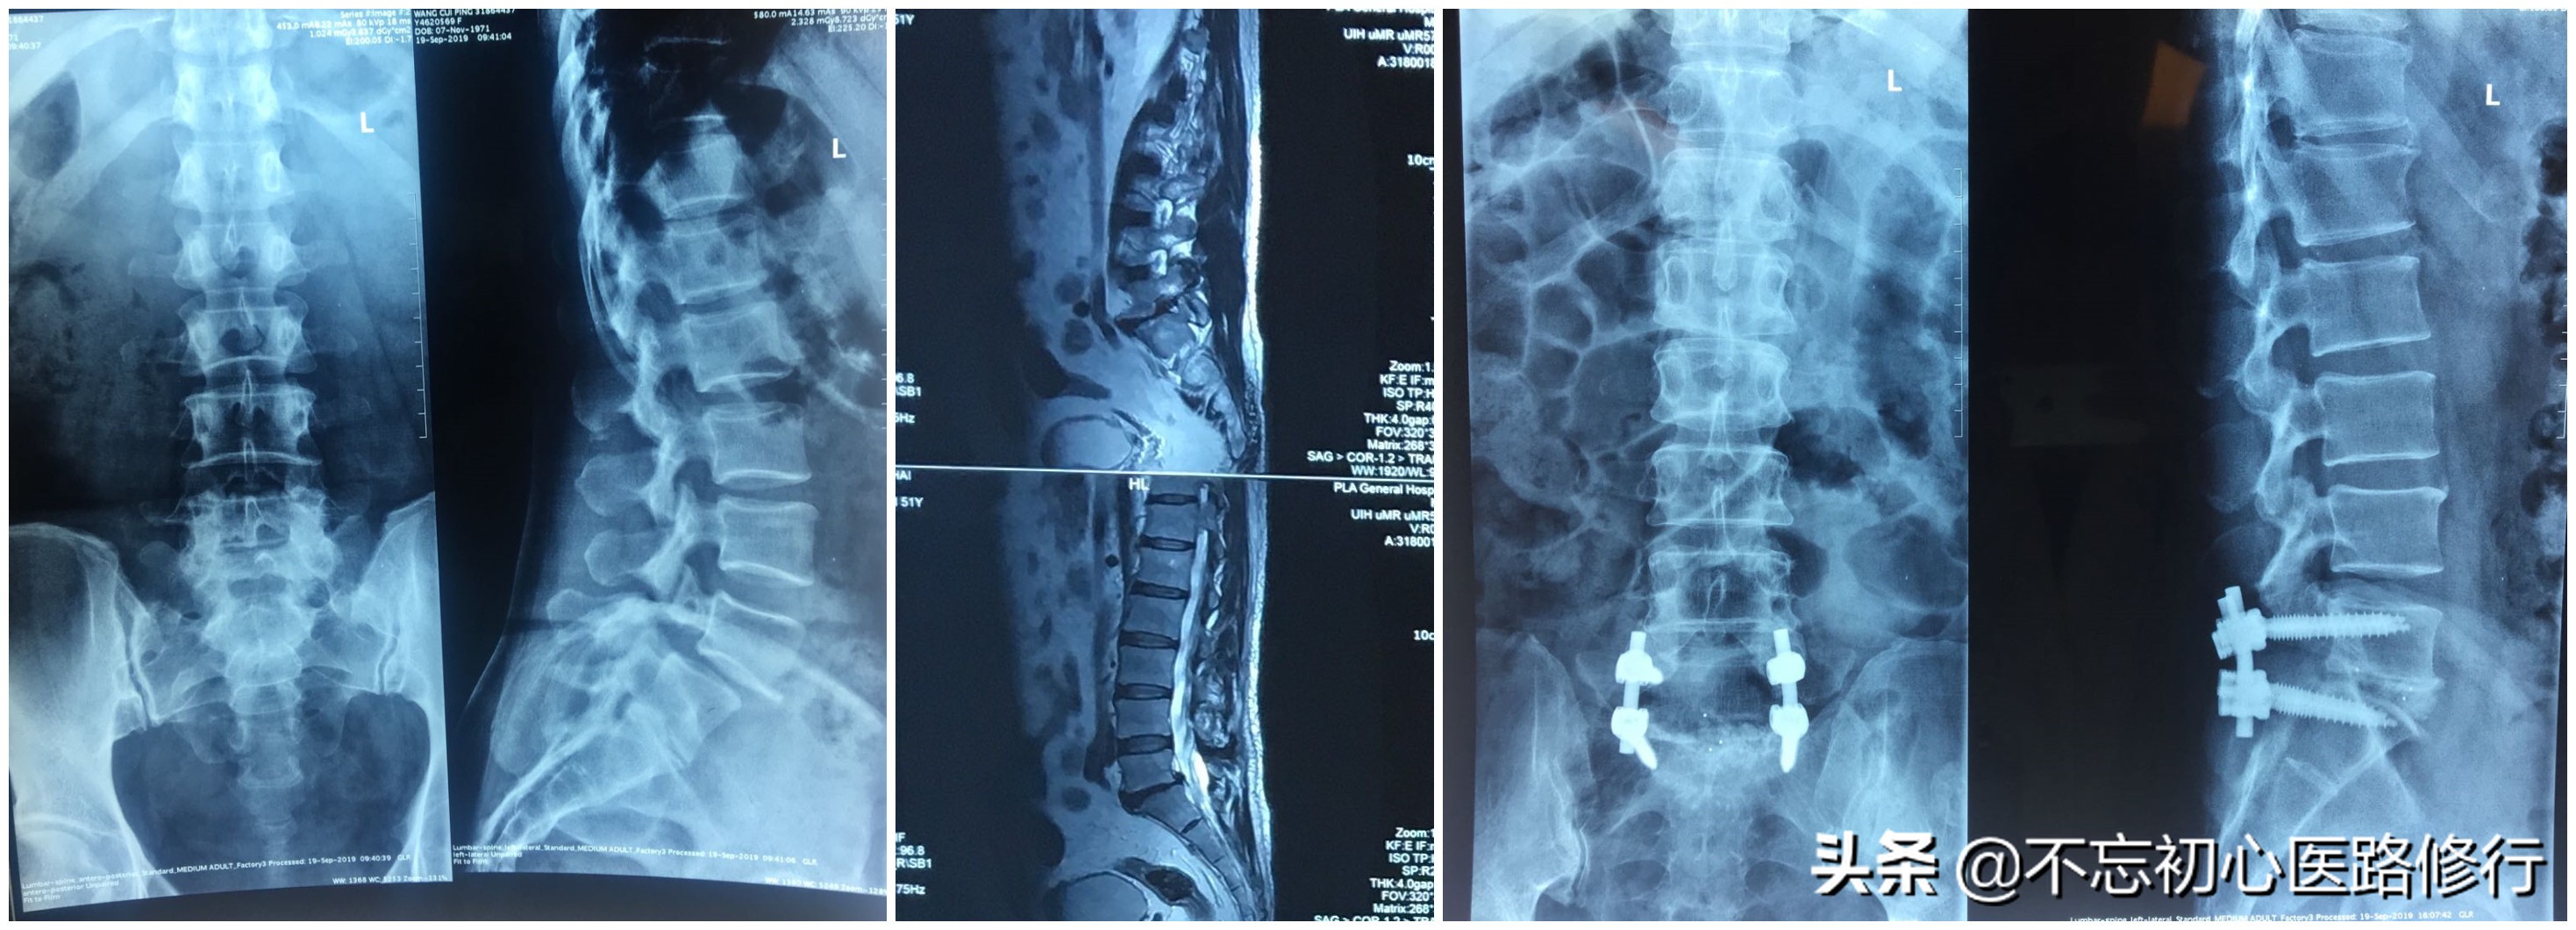

1.X线平片: 是最常规的检查,一般摄正侧位,若怀疑有不稳要摄屈伸动力位及双斜位。腰椎平片可完全正常,很多会出现:腰推侧弯、腰椎间隙宽度狭窄、腰椎生理前凸变小或消失,严重者甚至反常后凸,还可以看到纤维化钙化,骨质增生等。

2.CT检查: 能更好的显示脊椎骨性结构的细节。能清晰地了解到腰椎管的容积,关节突退变、内聚、侧隐窝狭窄以及黄韧带肥厚与后纵韧带骨化等。

3.MRI检查:能清楚的显示出人体解剖结构的图像,可以观察椎间盘的退变情况,髓核突出的位置和程度,有无椎管其他占位性病变等。

2、开放减压植骨融合手术: